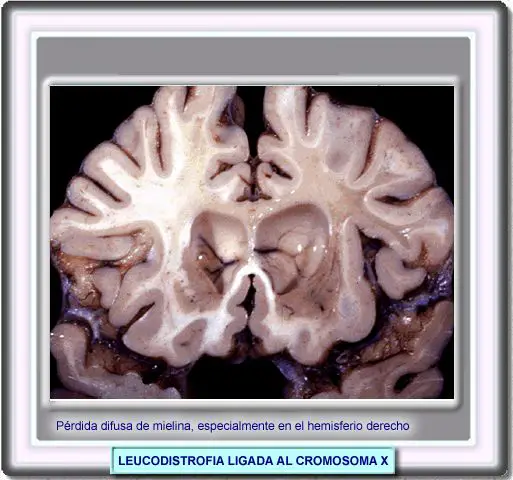

LEUCODISTROFIA LIGADA AL CROMOSOMA X

La primera comunicación sobre la adrenoleucodistrofia ligada al cromosoma X tuvo lugar en 1923. Siemerling y Creutzfeldt describieron un niños de unos 7 años que desarrolló piel bronzeada a los 4 años, seguida de una severa hiperpigmentación y disfunción neurológica con problemas de la marcha y del habla. El examen postmortem reveló una atrofia de la corteza cerebral con extensos cambios en la materia blanca unidos a una acumulación perivascular de linfocitos y células plasmáticas en el sistema nervioso lo que indicada un origen inflamatorio.